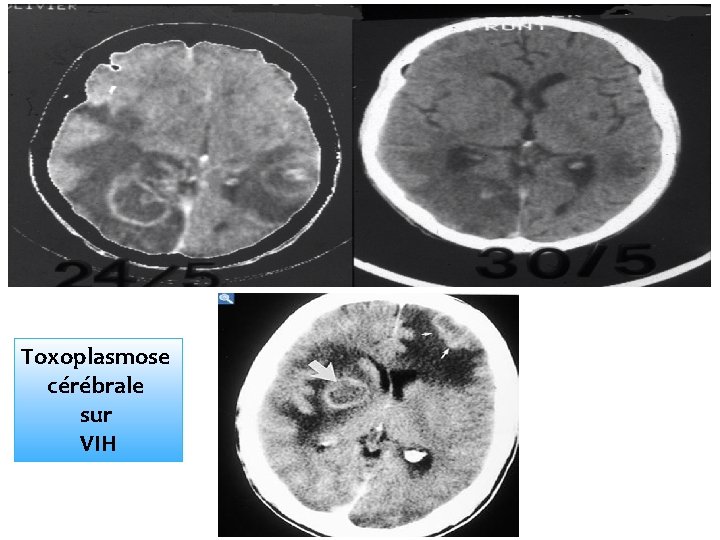

Toxoplasmose cérébrale sur VIH

DIAGNOSTIC 1. EXAMENS D’ORIENTATION : 1. 1. Formes Acquises : La formule numération sanguine montre une hyperleucocytose Un fond d’œil : systématique à la recherche de plages atrophiques rétiniennes, de choriorétinites et autres lésions ophtalmiques. La biopsie ganglionnaire montre une hyperplasie lymphoïde mixte à prédominance histiocytaire et à cellules hyperbasophiles. Autres examens physiques : contribuent pour une grande part dans le diagnostic de la maladie, surtout chez les immunodéprimés (lors de localisations cérébrales à savoir: l'électroencéphalogramme, la tomodensitométrie ou la résonance magnétique cérébrale).